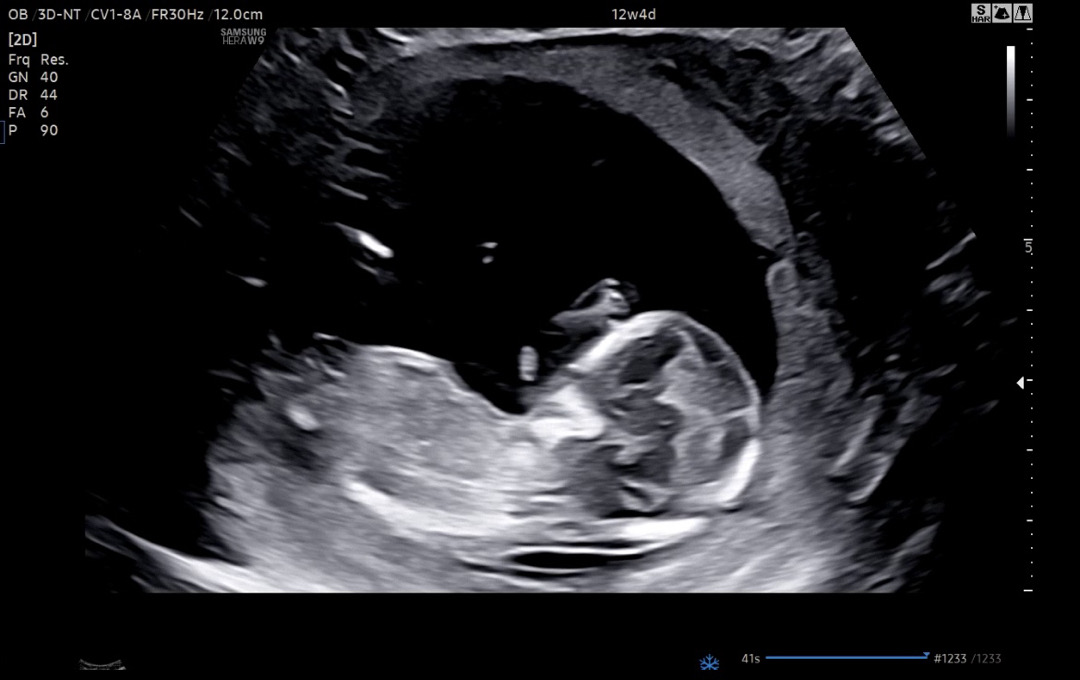

13주 각도법 봐주세용

병원에서 성별 대충이라도 말씀안해주셨는데 한달 못기다리겠어요 ㅠㅠ 제발 봐주세요 감사합니다